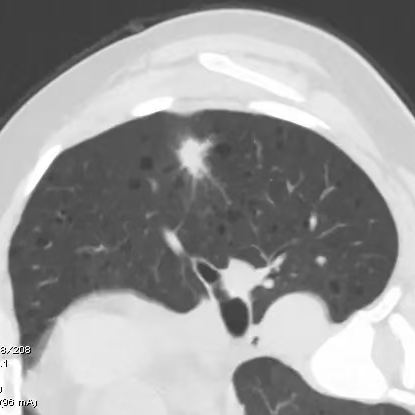

健康直通车: 健康是生命的宝贵财富,也是幸福生活的基石。为了更好地服务广大百姓,传播健康知识,葫芦岛市第二人民医院推出“健康直通车”专题栏目,将专业的医学知识以通俗易懂的方式传递给每一位市民,掌握科学的疾病预防方法,共同构筑健康中国的坚实基石。 什么是肺结节 肺结节是指肺内直径小于或等于3cm的类圆形或不规则形病灶,影像学表现为密度增高的阴影。大于3cm的称肿块。肺结节依其密度不同可分为实性结节、部分实性结节、磨玻璃结节,其中部分实性结节的恶性可能性最大,磨玻璃结节次之,实性结节尤其是小的实性结节结节最可能是良性的。 肺结节的常见病因 1、良性(约90%) 🔸 感染:结核、真菌、细菌性肺炎后遗留的瘢痕; 🔸 非感染:错构瘤(良性肿瘤)、炎性假瘤、血管瘤等。 2、恶性(约10%) 🔸原发性肺癌(如腺癌、鳞癌); 🔸转移性肿瘤(其他器官癌症转移至肺)。 如何根据影像判断肺结节性质 1、依据结节大小判断 🔸小于0.5cm的肺结节绝大多数都是良性的,属于微小结节。即使部分小于0.5cm肺结节是恶性的,但是适当的观察不影响预后。每年复查一次胸部CT就可以。 🔸大于0.5cm持续存在的纯磨玻璃结节,观察6个月,若持续存在,不管有无进展均多数是恶性的,视患者意愿,手术可以立即做也可观察至进展再做,不影响预后。 🔸大于0.8cm的部分实性结节恶性可能性非常大,应积极评估结节边缘毛刺、分叶、胸膜凹陷等征象。 🔸若实性部分大于0.5cm,恶性率显著提高。若在3~6个月随访期间实性部分增大或者总体部分增大,都可以考虑手术切除。而即使小于0.8cm的部分实性结节也需3个月就复查对比。 2、依据肺结节形态 如CT上提示病灶形态不规则、毛刺、分叶、胸膜凹陷、空泡征、血管集束征等,符合恶性肿瘤的征象。 🔸结节与正常肺组织之间界限非常清楚的恶性可能性大。 🔸结节密度不均呈混杂密度或均匀较大纯磨玻璃结节也基本是恶性的。 🔸有胸膜牵拉(不管是肺表面的脏层胸膜还是叶间裂部位的胸膜)的恶性可能性大。 🔸结节有浅分叶、细毛刺,密度较高而与周围肺组织边界不清的恶性可能性大。 🔸磨玻璃或混合磨玻璃结节存在小空洞的恶性可能性大。 🔸影像上似慢性炎表现,而没有炎症相关的其他异常,特别当所谓炎症区域内部或一侧与正常肺组织之间界限非常清楚的基本上是恶性的。 3、从结节发展情况来看 所有随访中增大进展的都需要考虑恶性可能,不进展而持续存在的纯磨玻璃结节也需考虑恶性。 葫芦岛市第二人民医院肺结节诊治中心孙振教授深耕肺结节领域四十余载,凭借对临床实践的执着钻研与深厚积淀,在肺结节精准诊断及鉴别诊断领域形成独到见解。他系统总结海量临床病例,创新性提炼出一套科学化、规范化的肺结节全周期诊疗体系,尤其在早期微小结节的影像特征识别、良恶性风险分层等方面积累了丰富经验,为众多患者提供了精准、高效的诊疗方案。 人民医院·人民名医 孙振 主任医师 三级教授 ·葫芦岛市第二人民医院胸外科主任、肺结节诊治中心主任 ·中国医科大学客座教授 ·原央企总医院著名胸外科专家 ·辽宁省医学会胸外科委员 ·辽宁省抗癌协会肺癌专业委员会委员 ·辽宁省细胞生物学学会食管癌专业委员会理事 ·主持多项科研成果获科技成果奖、科技进步奖、国家专科奖项 医学成就 从事胸外科临床工作近40年,担任胸外科首席专家及科室主任20余年,是我省胸外科领军人物,推动肺癌、食管癌等胸部肿瘤外科的规范化诊疗,在央企总医院牵头成立了肺结节诊疗中心,率先开展CT引导下肺内小结节定位切除,既确切完整切除肺内小结节,又降低肺功能损害。 专业特色 擅长肺癌、食管癌的外科手术和综合治疗,在各类高难度胸外伤手术治疗、胸腔镜微创手术、胸腺瘤手术及复杂并发症处理方面具有高深造诣,尤其擅长肺癌早期诊断,胸部小结节CT早期肺癌的鉴别等。完成各类高难度胸外科手术5000余例,其中微创手术占比达90%,治愈率达98%,多项业务填补省内空白。 开展的高难手术 胸腔镜肺部结节微创手术、肺癌根治术、食管癌根治术、各种纵隔肿瘤切除术、胸骨后甲状腺手术及胸部复合性外伤的抢救手术等。